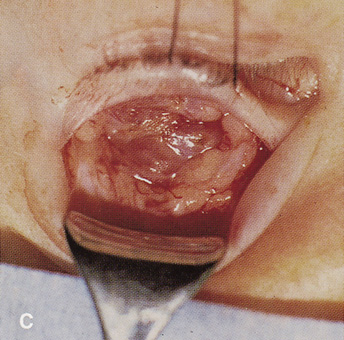

Fig. 14. A,B. Large intraorbital lymphangioma causing proptosis and optic nerve compression

in a 2-year-old child. C. View of the left orbit from above after removal of the frontal bone flap, including

the supraorbital rim and orbital roof. An extensive exposure

of the entire superior and lateral orbit is afforded. The levator

and superior rectus complex is being retracted laterally with a muscle

hook, whereas the Freer elevator retracts the superior oblique muscle

medially. The frontal nerve can be seen running from posterior to anterior

over the superior orbit. The orbital mass is exposed in this fashion. D. The fronto-orbital bone flap is wired back in place after completion of

the procedure. E. Postoperative appearance of the patient. F. The postoperative CT scan shows complete removal of the lymphangioma. This

large and diffuse lesion would have been difficult to remove with